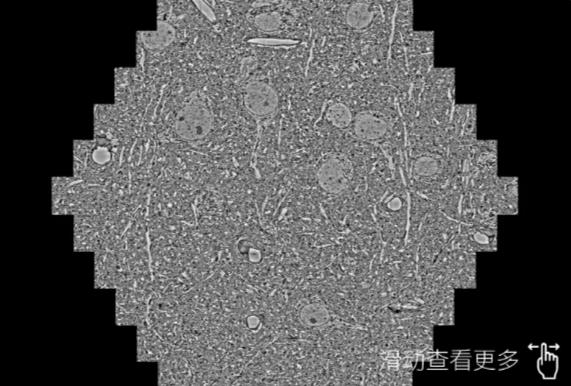

鼠脑切片。左图使用延边朝鲜族蔡司延边朝鲜族扫描电镜MultiSEM706对165μmx143pm面积区域成像,耗时仅需1.5秒。右图为鼠脑切片中30μm区域放大效果。样品由芝加哥大学B.Kasthuri提供。

使用蔡司高速延边朝鲜族扫描电镜MultiSEM对1mm²人脑皮层组织进行高分辨成像,并对其中的各种细胞结构进行三维重构分析。左图展示了2x3mm²组织平面中锥体神经元的三维重构效果。右图显示了局部体积神经元三维重构。图像由哈佛大学chtman实验室提供,渲染图由D. Berger 制作。